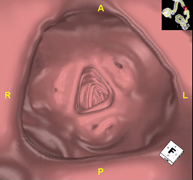

- Broncoscopia virtual La broncoscopia virtual es una técnica no invasiva que permite la visualización tridimensional y bidimensional de la tráquea y del árbol bronquial mediante la toma secuencial de imágenes captadas con TC Multidetector, obteniendo imágenes bi y tridimensionales. La calidad de las imágenes permite la navegación virtual por el interior de la tráquea y de los bronquios gracias al procesamiento en estaciones de trabajo especializadas. La broncoscopia virtual es una técnica no invasiva que permite la visualización tridimensional y bidimensional de la tráquea y del árbol bronquial mediante la toma secuencial de imágenes captadas con TC Multidetector, obteniendo imágenes bi y tridimensionales. La calidad de las imágenes permite la navegación virtual por el interior de la tráquea y de los bronquios gracias al procesamiento en estaciones de trabajo especializadas.